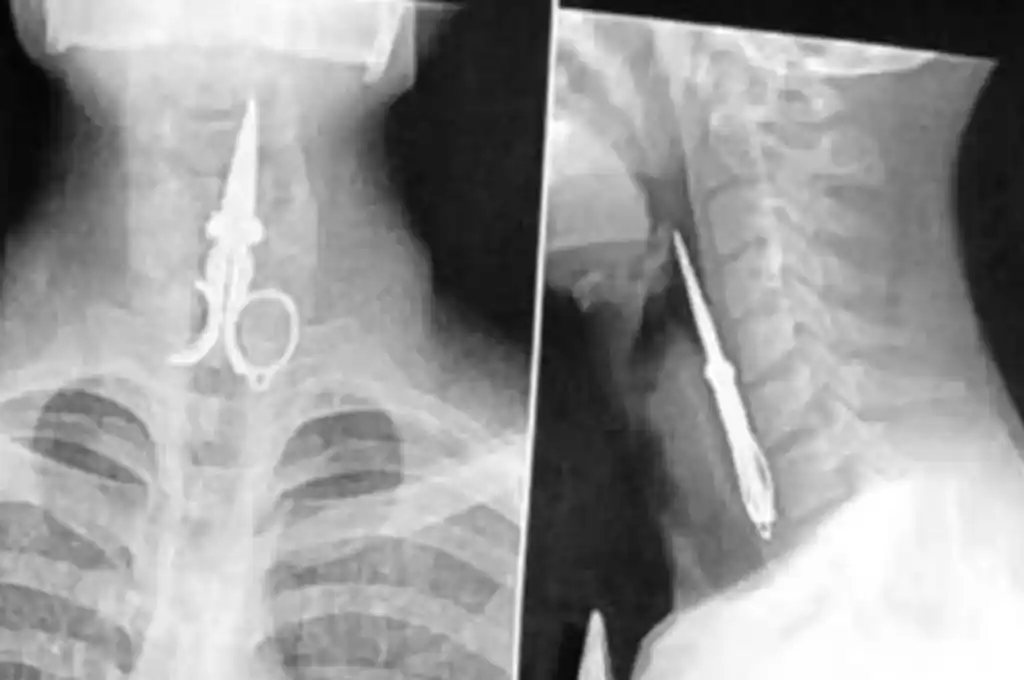

Un incidente impactante ocurrió en la cárcel de San Juan, donde Axel Hernán Rojas, un preso que cumple condena desde 2019 por delitos contra la propiedad, se tragó la mitad de una tijera como forma de protesta. Este acto extremo no es el primero en el que Rojas se ha involucrado, ya que en 2021 se cosió la boca antes de enfrentar su juicio, lo que obligó a las autoridades a intervenir para brindarle asistencia médica.

El incidente ocurrió en el penal de Chimbas, donde Rojas ingirió el objeto metálico de manera deliberada, lo que llevó a una rápida intervención del personal penitenciario. Tras recibir la autorización del Juzgado de Ejecución Penal, Rojas fue trasladado a un hospital para una revisión médica. Aunque se negó a recibir atención, los profesionales determinaron que no era necesaria una intervención quirúrgica, ya que pudo expulsar la tijera por sus propios medios.